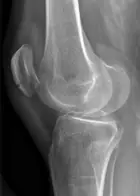

Genou

Entorse de genou

Fracture de patella

Luxation de genou